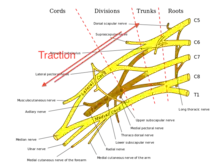

Axillary, Median, Musculocutaneous, Radial, Ulnar.

The brachial plexus is made up of spinal nerves that are part of the peripheral nervous system. It includes sensory and motor nerves that innervate the upper limbs. The brachial plexus includes the last four cervical nerves (C5-C8) and the 1st thoracic nerve (T1). Each of those nerves splits into smaller trunks, divisions, and cords. The lateral cord includes the musculocutaneous nerve and lateral branch of the median nerve. The medial cord includes the medial branch of the median nerve and the ulnar nerve. The posterior cord includes the axillary nerve and radial nerve.[21]

Traction

Traction occurs from severe movement and causes a pull or tension among the nerves. There are two types of traction: downward traction and upward traction. In downward traction there is tension of the arm which forces the angle of the neck and shoulder to become broader. This tension is forced and can cause lesions of the upper roots and trunk of the nerves of the brachial plexus.[22] Motorcycle accidents and sports injuries usually cause this type of injury to brachial plexus.[12] Upward traction also results in the broadening of the scapulo-humoral angle but this time the nerves of T1 and C8 are torn away. Humeral fractures and shoulder dislocations can also cause this type of injury with high energy injuries.[12]